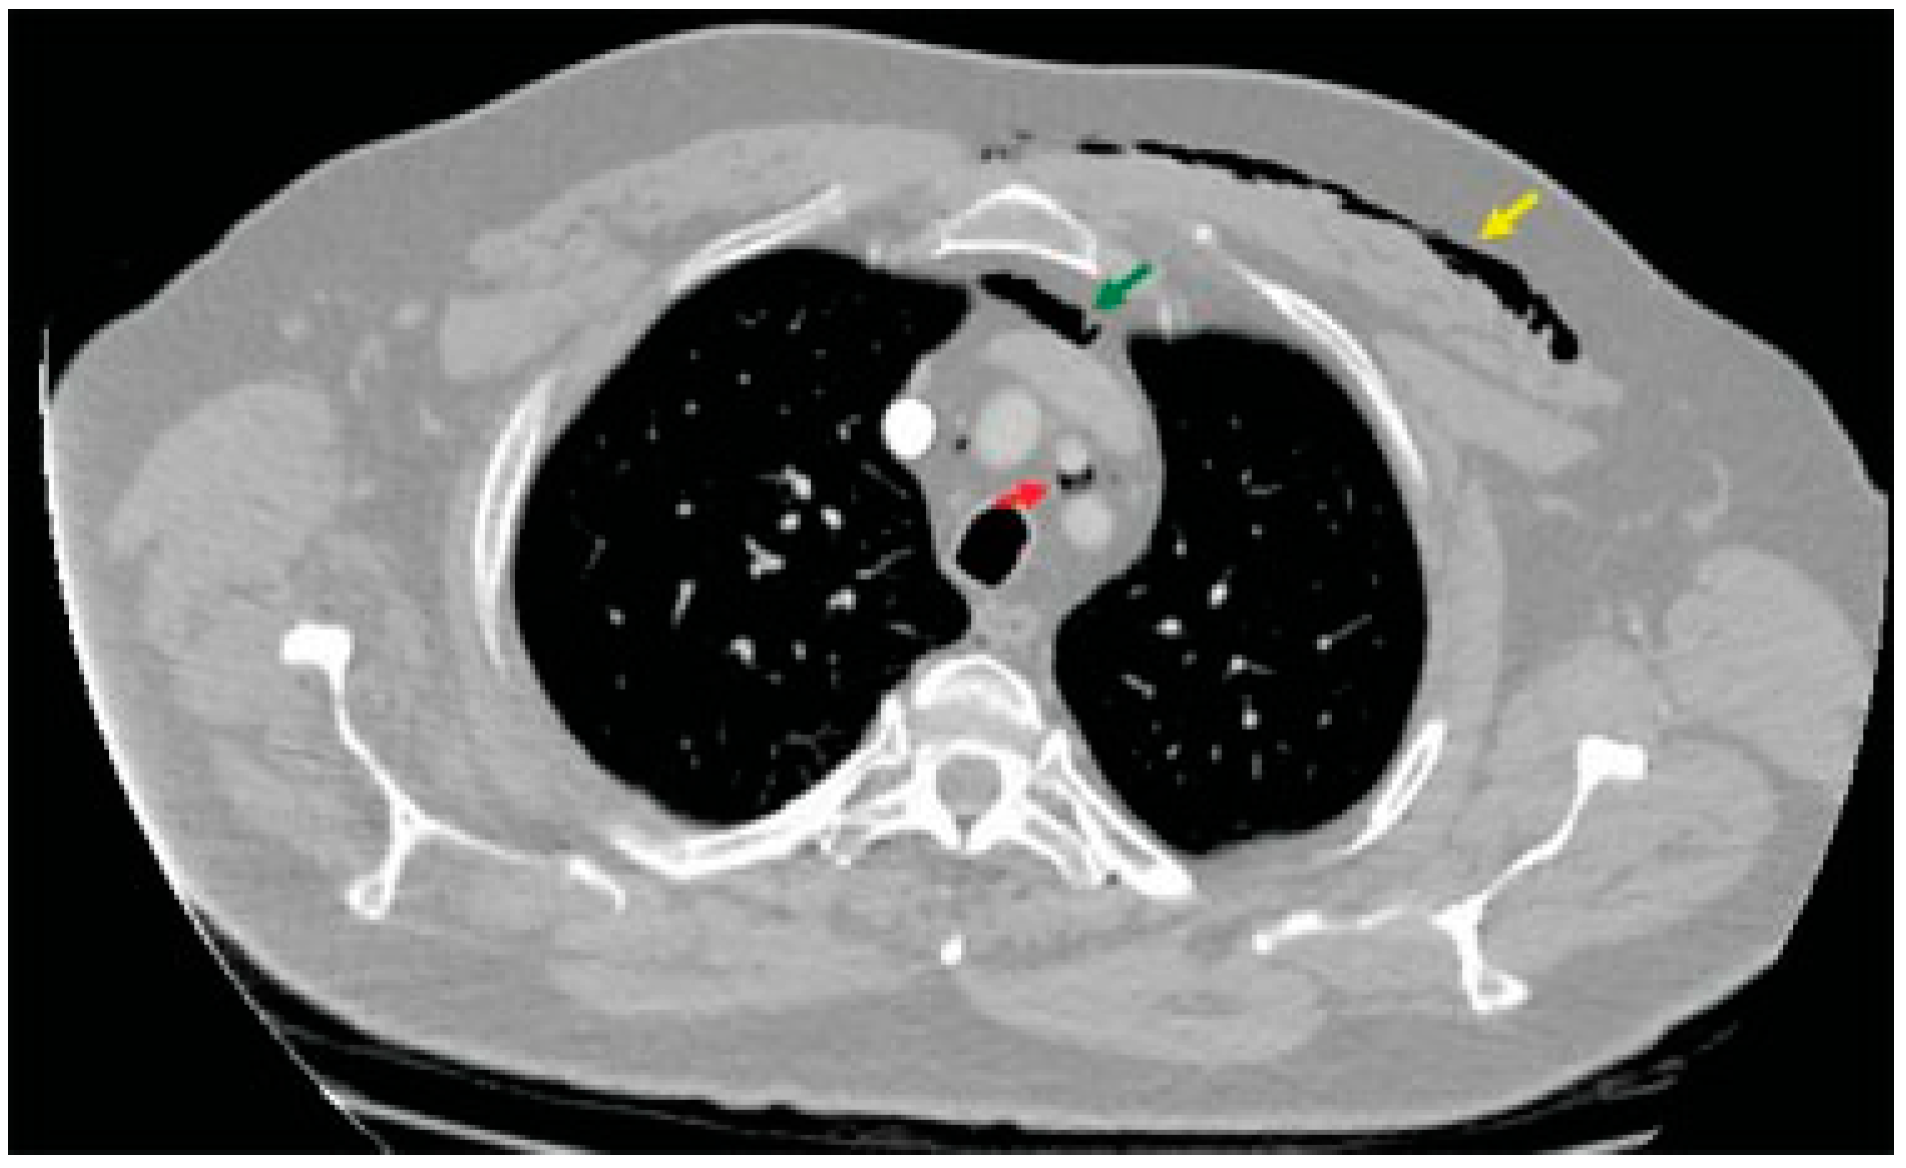

Case Report